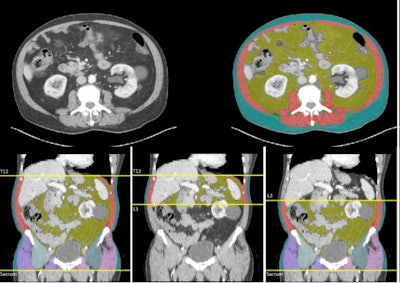

Examples of CT volumetric and single-slice images produced by Data Analysis Facilitation Suite (DAFS) v3.9 software are displayed.Examples of CT volumetric and single-slice images produced by Data Analysis Facilitation Suite (DAFS) v3.9 software are displayed.Figure courtesy of Dr. Daniel Jeong and EJR.

The single-slice CT analysis of the mid-third lumbar (L3) vertebral axial that is commonly used for this analysis, while consistent, has the limitation of not capturing the variable distribution of abdominal fat and muscle.

The authors, led by radiologist Dr. Daniel Jeong, used three boundaries to estimate muscle and fat distribution for the volumetric body composition metrics: the total (T12-sacrum), upper abdomen (T12-L3), and lower abdomen/pelvis (L3-sacrum). They noted that the upper and lower abdominal metrics were evaluated separately because fat and muscle compartments are not evenly distributed across the abdomen, and region-specific metrics may provide refined, more-specific information. All output was reviewed by a board-certified abdominal radiologist with several years of experience to ensure accurate segmentation analysis.